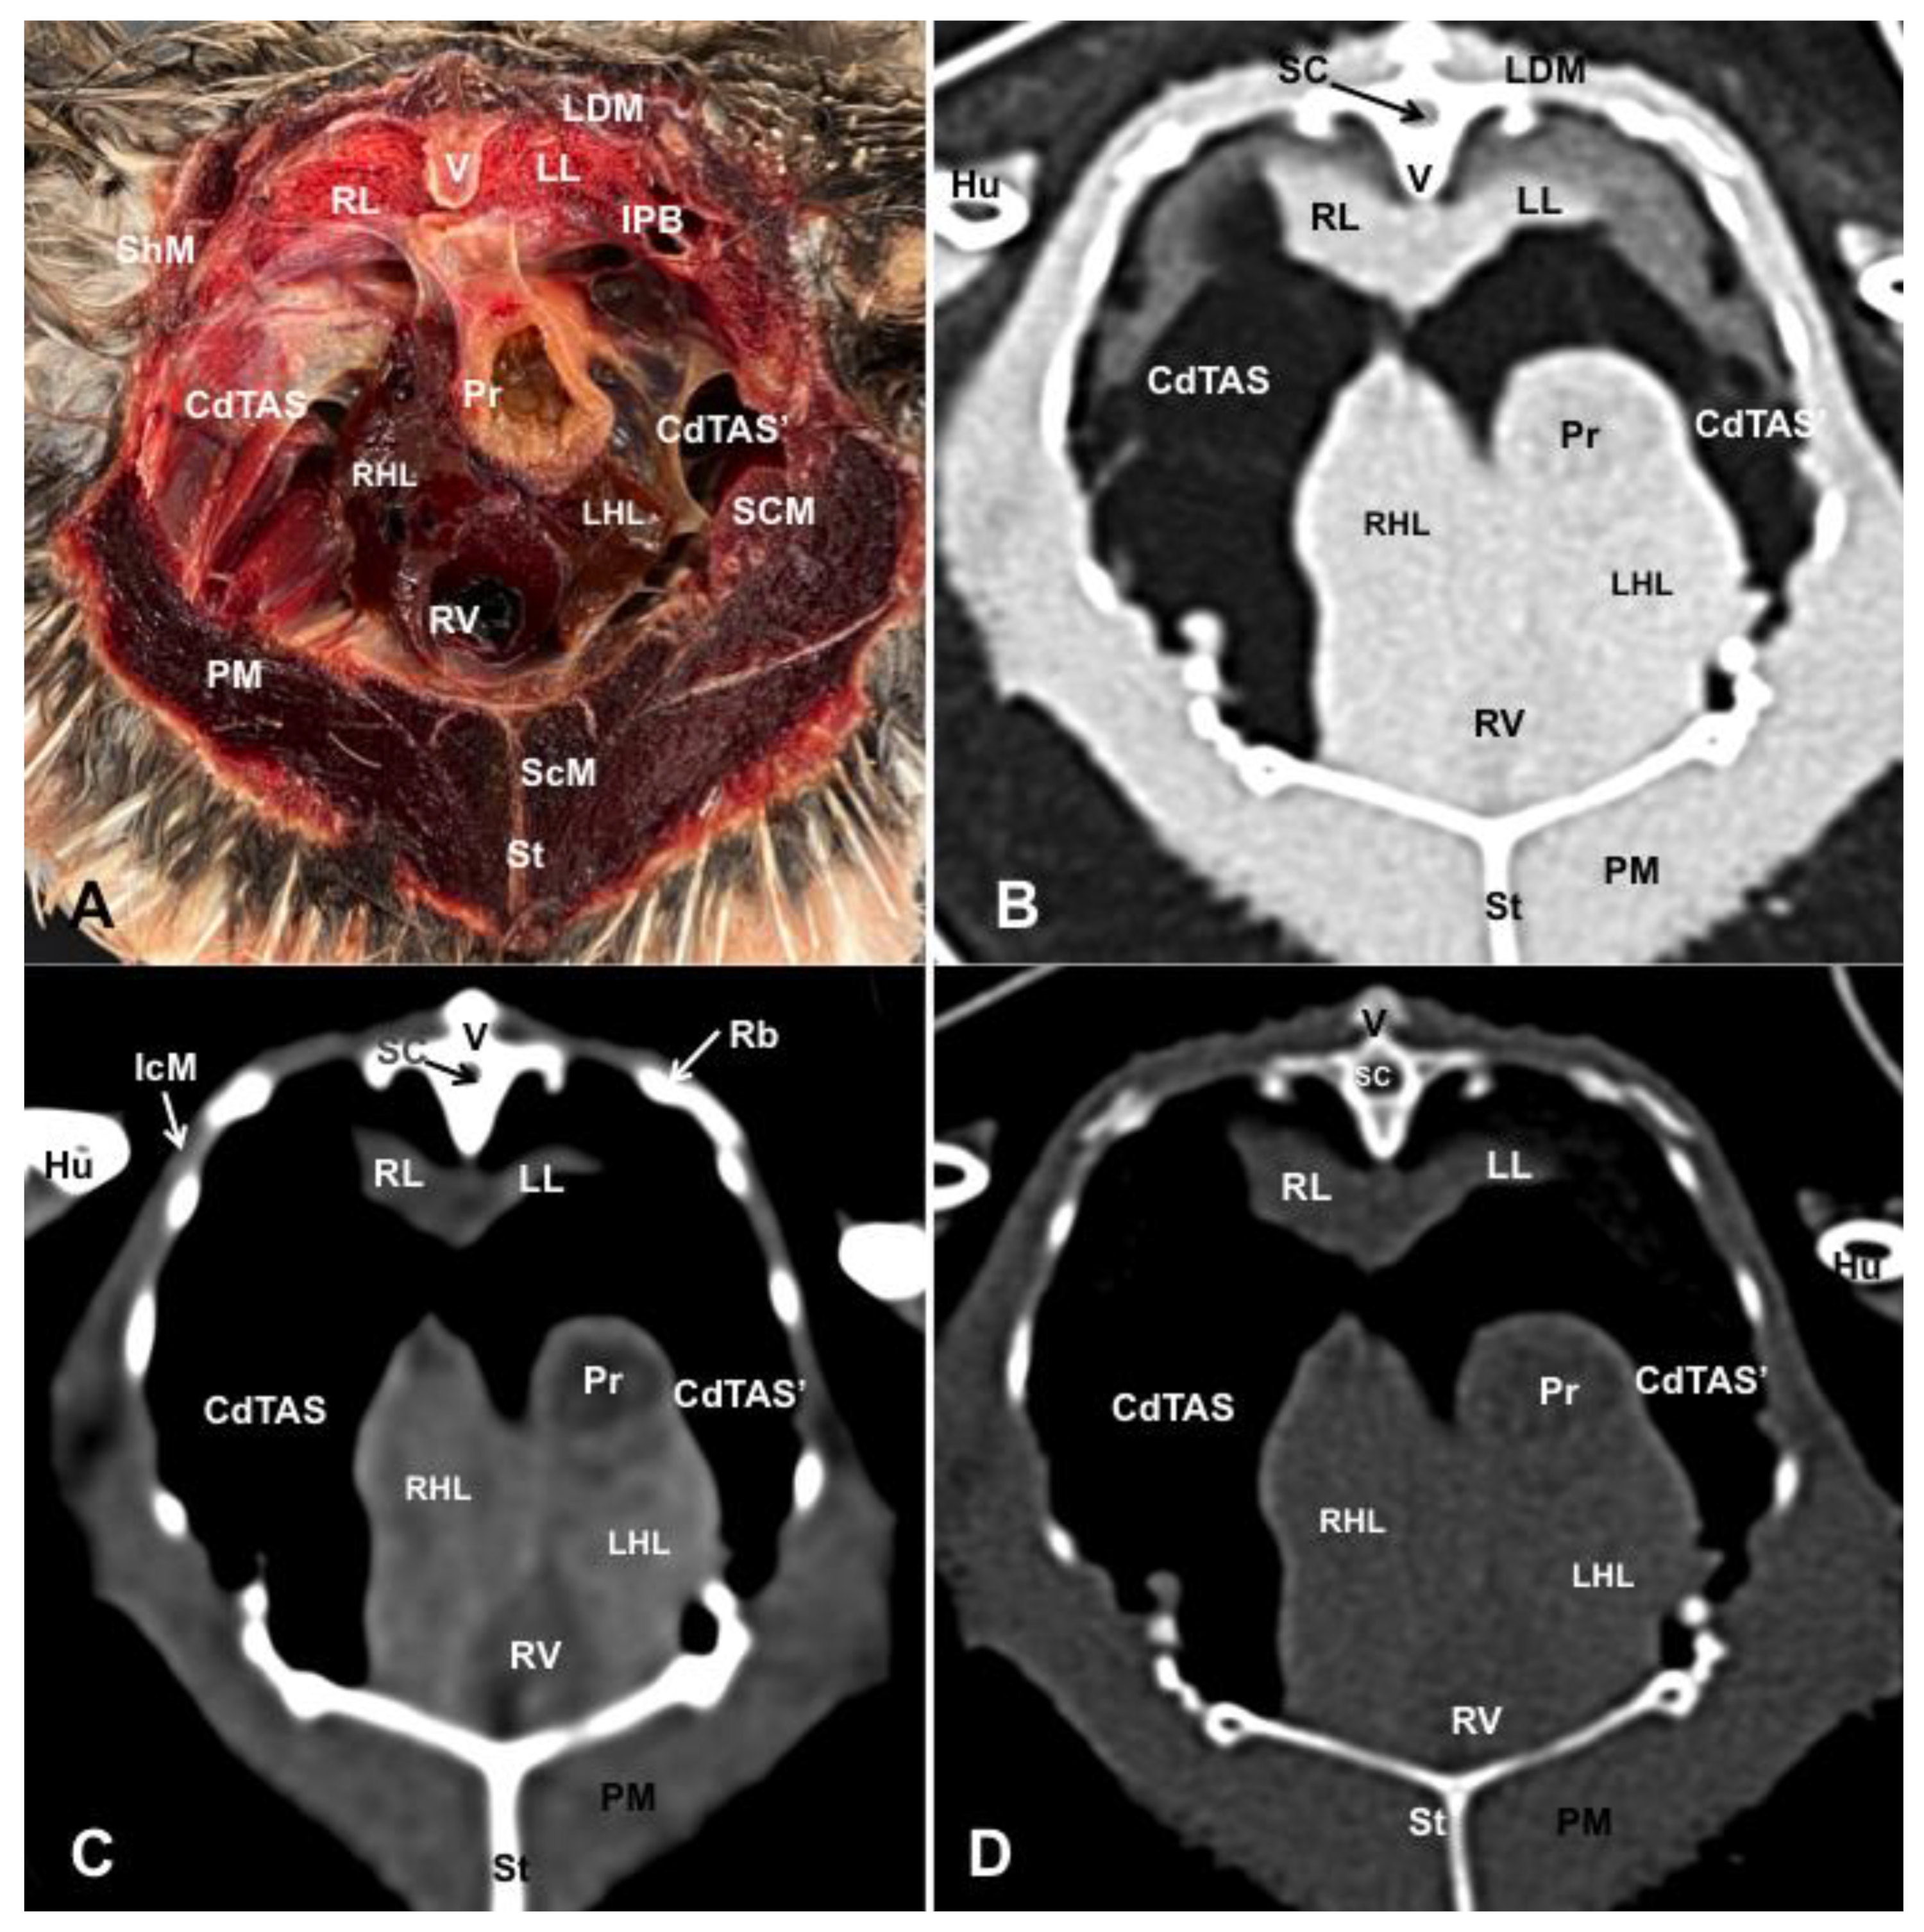

3.1. Anatomical Dissections and Cross-Sections

3.2. Computed Tomography Images